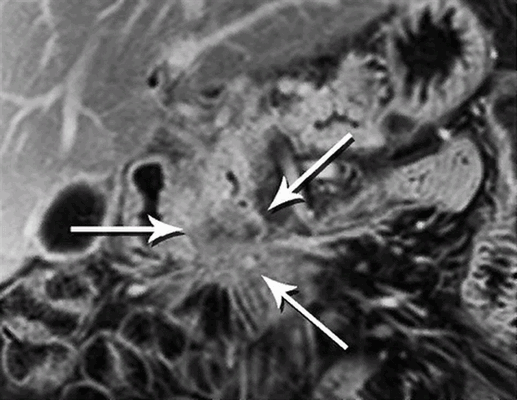

МРТ: А - резкое изменение просвета панкреатического протока - косвенный признак опухоли тела поджелудочной железы небольшого размера. В - снимок, сделанный в артериальную фазу МР-ангиографии, при увеличении демонстрирует новообразование, вызывающее обструкцию протока (толстая стрелка), тонкая - печеночная артерия, короткая - верхняя брыжеечная артерия